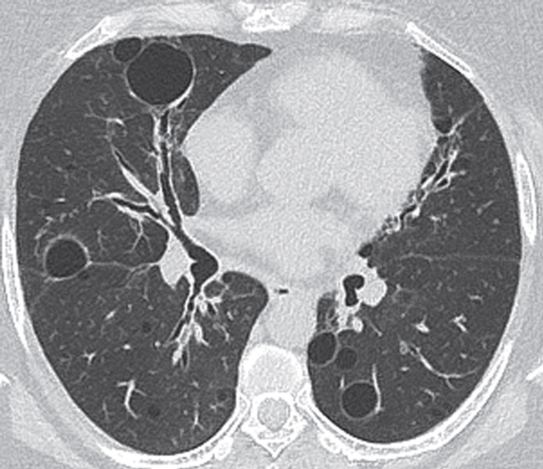

PLCH 最初的HRCT表现为小叶中心或细支气管周围结节,通常直径1-10毫米,边缘不规则。随着病情的发展,结节发生囊变。结节和囊肿常并存(图1A ),常可确诊。在晚期,囊肿占多数,数量和大小不一,不规则,形状各异,并可融合( 1B)。起初,囊肿的壁很厚,后来囊变薄。囊性病变主要发生在上叶,不累及肋膈区域( 1 c)。气胸发生率高达15%( 1D)(3,6) 推测囊肿是由细支气管壁炎症引起的气道扩张、结节空洞化或纤维病变牵引起的空腔扩大而形成。继发改变包括肺动脉高压,可以CT观测到如肺动脉干和左右肺动脉增

1 肺朗格汉斯组织细胞增多症的CT 表现A 上叶不规则囊肿和边缘不规则的小叶中央结节( ) B不规则薄壁囊肿( 轴位)C不规则囊肿主要在上叶,且不累及肋膈区域( 冠状面)D不规则囊肿,一些小叶中心结节,左侧气胸( 轴位)